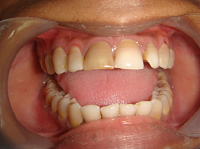

In the present study, the ability of mineral trioxide aggregate in the formation of apical plug for healing of large periapical lesion with open apex was assessed and evaluated the clinical outcome. Fifteen participants with periapical lesion at the upper anterior teeth with open apex were treated with mineral trioxide aggregate. The effect on healing of apical size was evaluated at 3, 6, and 12 months by radiological examinations in the form of periapical index criteria, diameter of the lesion size and the presence or absence of apical tissue barrier. The results found that neither pain nor any sinus was detected at 12 months. The mean size of the apical lesion was gradually reduced from 5.1 × 3.8 to 1.5 × 0.9 mm and mean PAI was reduced from 3.3 to 1.7 mm. The differences between mean size of periapical lesion at preoperative and 12 months observation period was also statistically significant (p<0.05). The clinical success shown significant success rate of 93.3% analyzed with Z-test. In conclusion, tooth with open apex can be successfully treated with mineral trioxide aggregate apexification technique followed by root canal obturation.